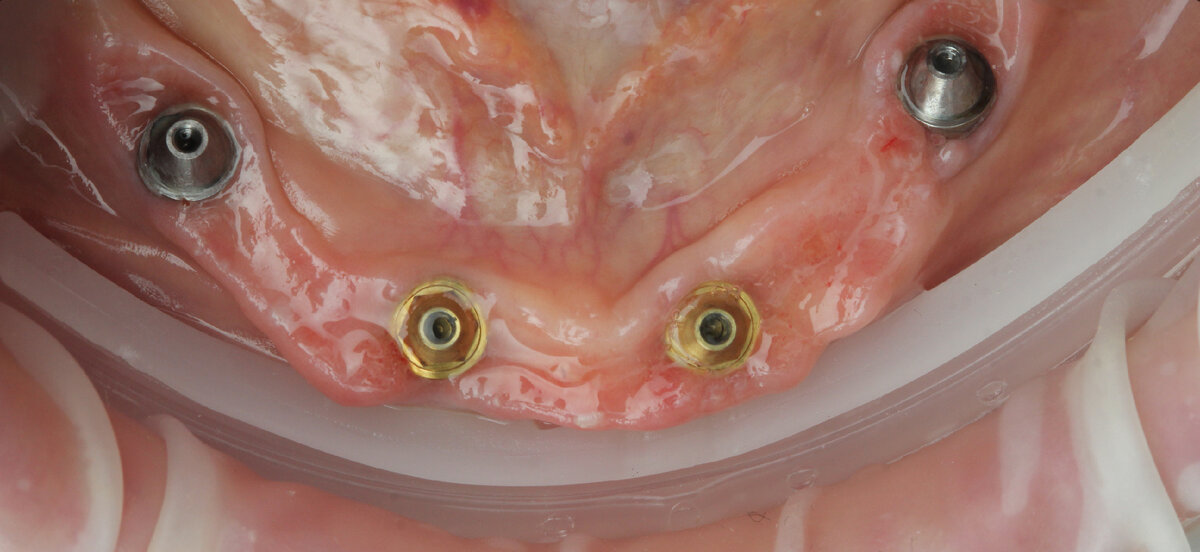

Ложка с трансфер-чеками отправляется на снятие нового, рабочего!, слепка.

Снятые Доктором новые данные:

По подтвержденной постановке - изготовлена титановая балка, установлены зубы и произведена варка протеза: